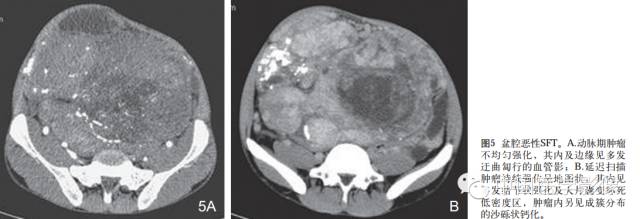

1.外形及囊变坏死:良性SFT一般为边界清晰的单发肿块无分叶或浅分叶,肿瘤大多呈实性,囊变坏死区较小。恶性SFT一般为囊实性或囊性为主肿块呈分叶状坏死范围广泛。

2.密度或信号特点:肿瘤实性部分CT表现为软组织密度,囊变坏死区呈低密度。位于胸腔的SFT尽管体积巨大,但密度相对均匀,坏死少见且范围多较小。良性肿瘤坏死少见,恶性肿瘤不规则坏死区相对多见。腹部SFT都有不同程度的坏死囊变和钙化。MRI除了能够提供明确肿瘤的确切部位及累及范围外,对于明确肿瘤的组成成分具有重要价值。MR信号改变与肿瘤的组织学特征密切相关,其内成熟的纤维组织在T1WIT2WI序列上均呈低信号,而肿瘤细胞及血管聚集区则呈等T1长T2信号,因此T1WI一般为等信号或低信号T2WI多为混杂信号。文献认为T2WI低信号对于本病诊断具有重要价值。

3.包膜:良性孤立性纤维性肿瘤多具有明显的包膜,文献报道包膜出现率约50%。包膜出现可能与肿瘤缓慢生长过程中对周围正常组织缓慢压迫有关。

5.钙化:少见,文献报道部分病灶内可发生斑点、斑片状钙化,常发生在较大的肿瘤,可能与肿瘤坏死有关。

6.增强扫描:SFT为富血供肿瘤,增强扫描呈肿瘤实性部分呈地图样明显强化、延迟扫描进一步强化是SFT的主要特征。病灶实性部分显著强化与镜下血管外皮瘤样分布区及细胞密集区有关,而肿瘤内部坏死囊变区不强化。此外,细胞稀疏区与胶原纤维束玻璃样变区域强化相对较弱,因此形成地图样不均匀强化表现。持续性强化的模式可能与病灶内胶原纤维缓慢强化有关,还可能与黏液样变及细胞疏松排列导致细胞外间隙扩大对比剂在细胞外间隙内进行性聚集有关,因此动态扫描对于本病的诊断具有重要价值。